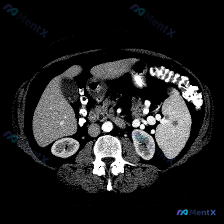

最近看到一份很有意思的腹部增强CT病例,核心发现是脾脏的一个低密度灶,感觉很容易在诊断上走偏,整理了一下完整的分析思路和大家分享。 一、先看完整的影像表现(核心事实) 这是一次增强扫描(动脉晚期/门脉期),图像质量挺好: 1. 脾脏:实质中部见一类圆形低密度影,边界尚清,周边未见明显强化(划重点)。...